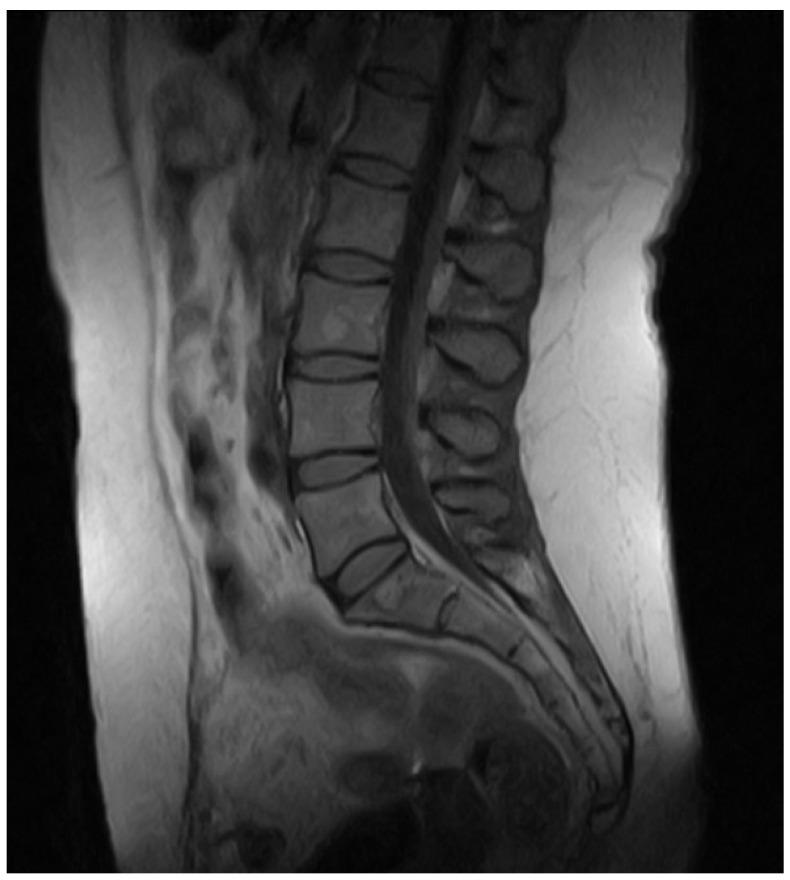

This article presents the case of a 43-year-old woman with Chiari malformation 1B who underwent resection of the filum terminale. She presented as an outpatient at the University Hospital "G. Martino" in Messina, complaining of difficulty walking, balance problems, lumbar pain, and heaviness in the lower limbs. Following a multidisciplinary assessment, she underwent an 11-month rehabilitation protocol based on cognitive therapeutic exercise.

本文介绍了一名43岁患有1B型Chiari畸形的女性患者,她接受了终丝切除术。她在墨西拿的“G. Martino”大学医院门诊就诊,主诉行走困难、平衡问题、腰痛和下肢沉重感。经过多学科评估后,她接受了为期11个月的基于认知治疗性锻炼的康复方案。